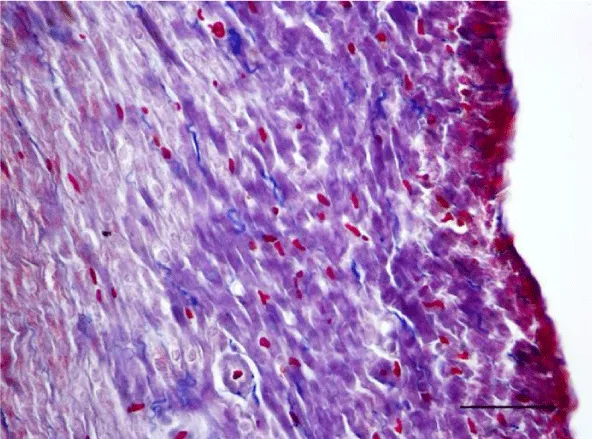

Mallory’s trichrome stain in young rats revealed an insignificant number of fine collagen fibers present predominantly in the perivascular zone and in the wall of the blood vessels in the left as well as the right ventricle (Figures 9,10). Collagen fibers were also visualized in the interstitial space and the perimysium, where their quantity was less and their alignment was not strictly organized. In the left ventricle of three-month-old animals they were fairly thicker and had a spiral shape unlike those in the left ventricle of one-month-old rats (Figure 11). They are relatively shorter and fewer in number. In the wall of the left ventricle within both age groups we noted extremely short and few collagen fibers located in the interstitial space (Figure 12). Thin and short fibrous fascicles were seen extending from the perivascular space among the cardiomyocytes in both ventricles.